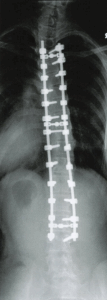

目的:金属インプラント(スクリュー・フック・ロッド等)で変形を三次元的に矯正して固定し、骨癒合を得る。

後方法(標準):正中切開→椎弓根スクリュー等で強固に把持し、ロッドで回旋を含め立体矯正。

前方法:胸腰椎・腰椎の一部シングルカーブ等に選択。前方解離+プレート/スクリュー+ロッド。

固定下端(LIV):将来の腰椎変性を抑えるため、可能ならL3以上を目標に計画(症例により異なる)。